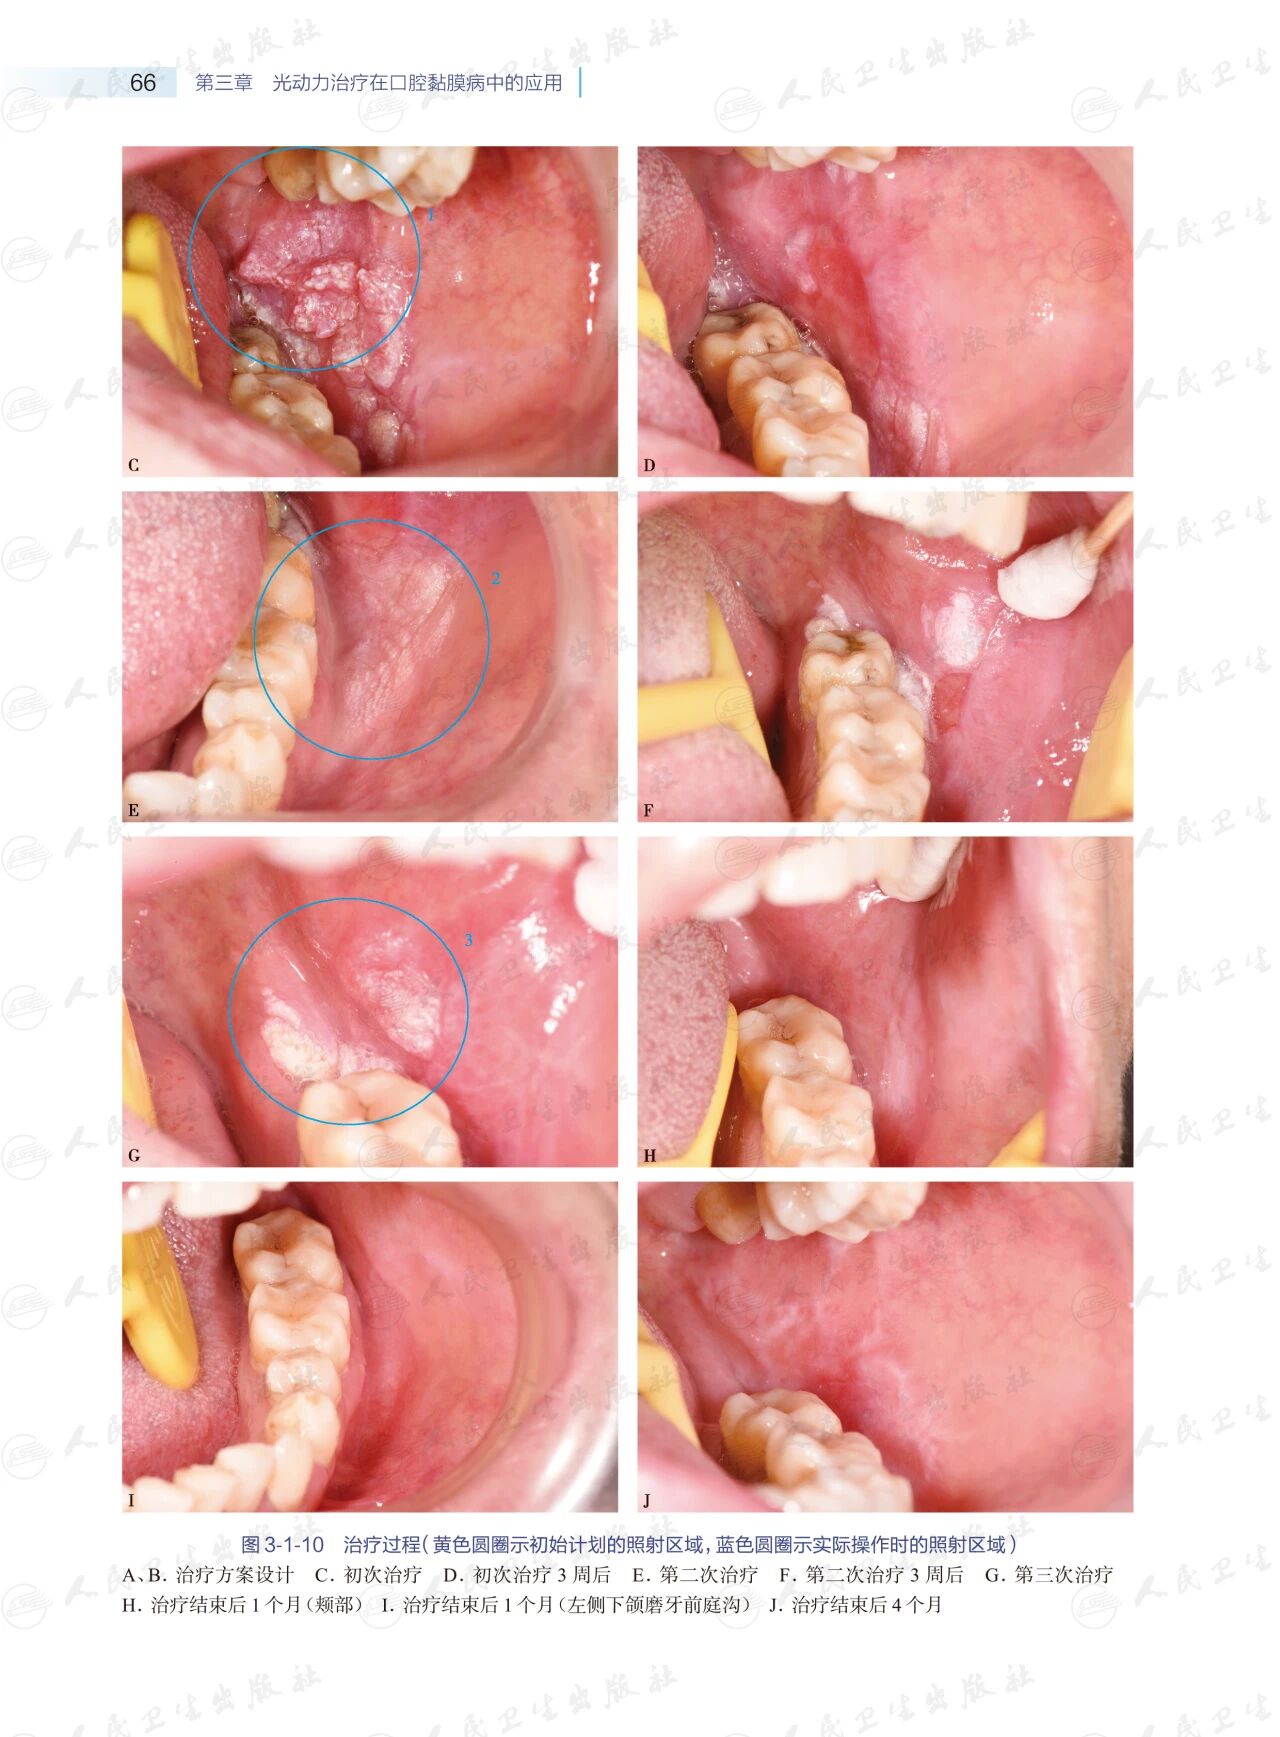

3本书首先介绍了光动力治疗的基本理论和口腔黏膜病光动力治疗的操作规范,继而结合临床案例,重点展示了光动力治疗在不同部位、不同类型口腔黏膜病中的实际应用,并针对目前口腔黏膜病的光动力治疗尚未解决的问题提出了未来可能的发展方向。

4全书23.9万字,280余幅临床高清照片,23个临床案例,图文并茂,指导性及实用性强。